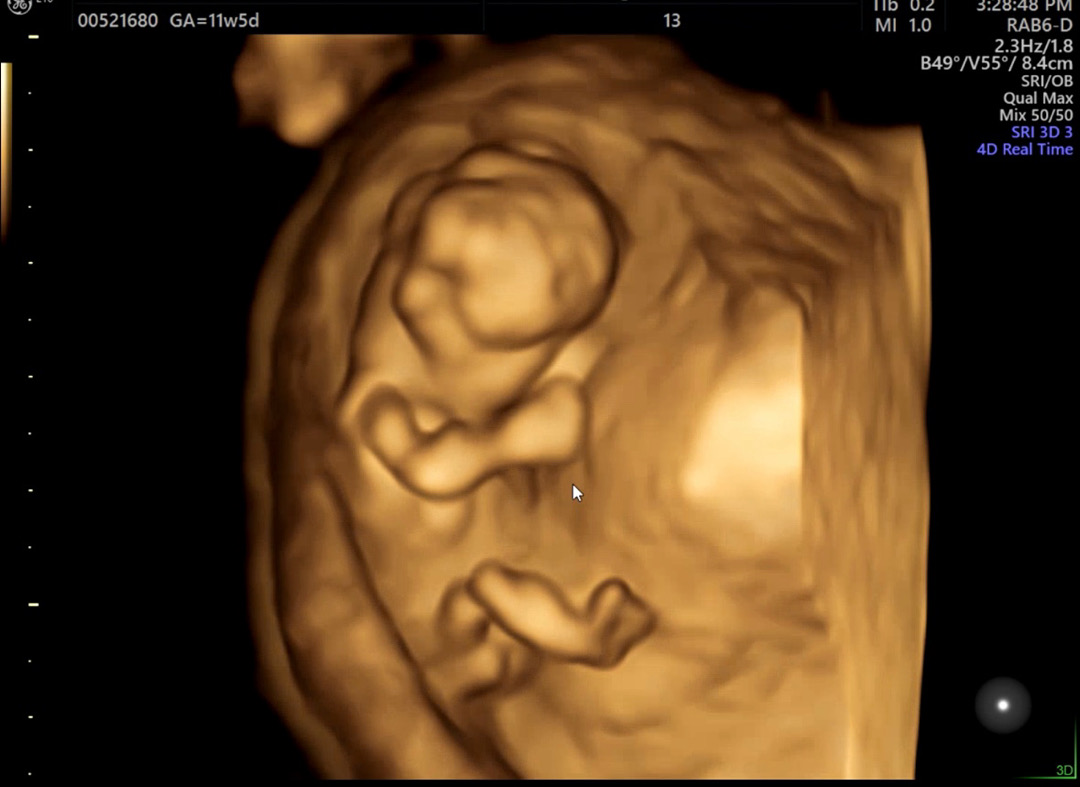

오늘 11주 5일로 정밀초음파를 보고왔는데요! 아가가 옆으로 잘안누워서 각도법?으로는 잘 모르겠고 입체초음파로 보면 아래가 갈라져있긴하던데...아직 모르는거겠죠..? 🙄정보 아시는분있으면 댓글 부탁드리겠습니다☺️

입체초음파 성별